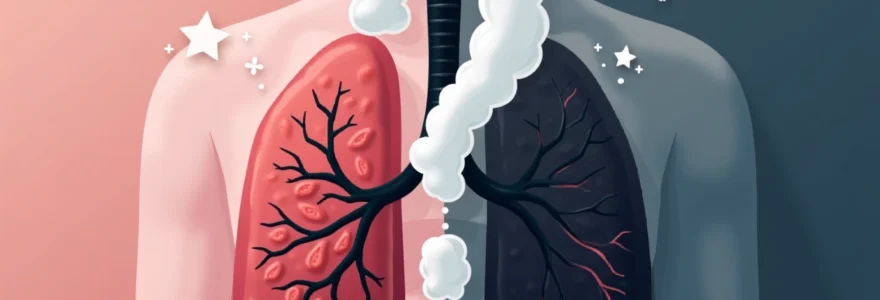

Radio Poumon Fumeur Vs Poumon Sain

La différence, elle est là, juste dans le son, dans l'énergie. Le poumon fumeur, il lutte un peu, il fait de son mieux avec ce qu'il reçoit. Il a ses moments de bravoure, mais il est souvent essoufflé. Le poumon sain, lui, il danse. Il est léger, il accueille chaque inspiration comme un cadeau. C'est une question de respect pour soi-même, non ?

Gallery